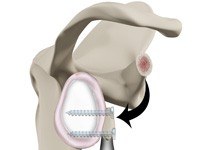

Latarjet

The shoulder joint provides a wide range of movement to the upper extremity but overuse or trauma can cause instability to the joint. The Latarjet procedure is a surgical procedure performed to treat shoulder instability by relocating a piece of bone with an attached tendon to the shoulder joint.